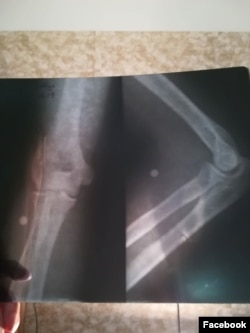

გიორგი პოლიციისთვის წართმეული ფარით იცავდა თავს, ფეხებს რუსთავი ორის ბანერი უფარავდა.როცა ტყვიები ბანერს დაუშინეს, ღამის 2 საათი იქნებოდა. ტყვიებისგან თავის დასაცავად უკან სვლა დაიწყო და როგორც კი მისი მარჯვენა ხელი ბანერიდან გამოიწია, 5 ტყვია მოხვდა. ერთი თვითონვე ამოიღო. დანარჩენისთვის მეცხრე საავადმყოფოში გადაიყვანეს. იქ შეხვდა რობის და სხვა დაჭრილებს.

ამბობს, რომ ქირურგი ყველას ზედაპირულად ათვალიერებდა, მისი ტყვიებიც არ ამოუღია სხეულიდან, ჭრილობები მხოლოდ გადაუხვიეს და რენტგენი გადაუღეს და გამოწერისას უთხრეს, რომ 243 ლარი ჰქონდა გადასახდელი. საავადმყოფო მეორე დილით დატოვა, ფული, რომელსაც ითხოვდნენ, კერძო დაზღვევამ აუნაზღაურა, აქციაზე მოხვედრილი ტყვიების ამოსაღებად კი სხვა ექიმთან მივიდა.